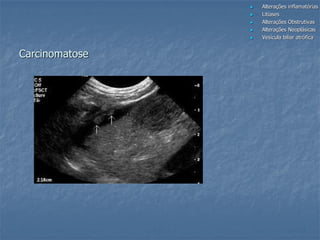

Carcinoma biliar

Carcinomatose